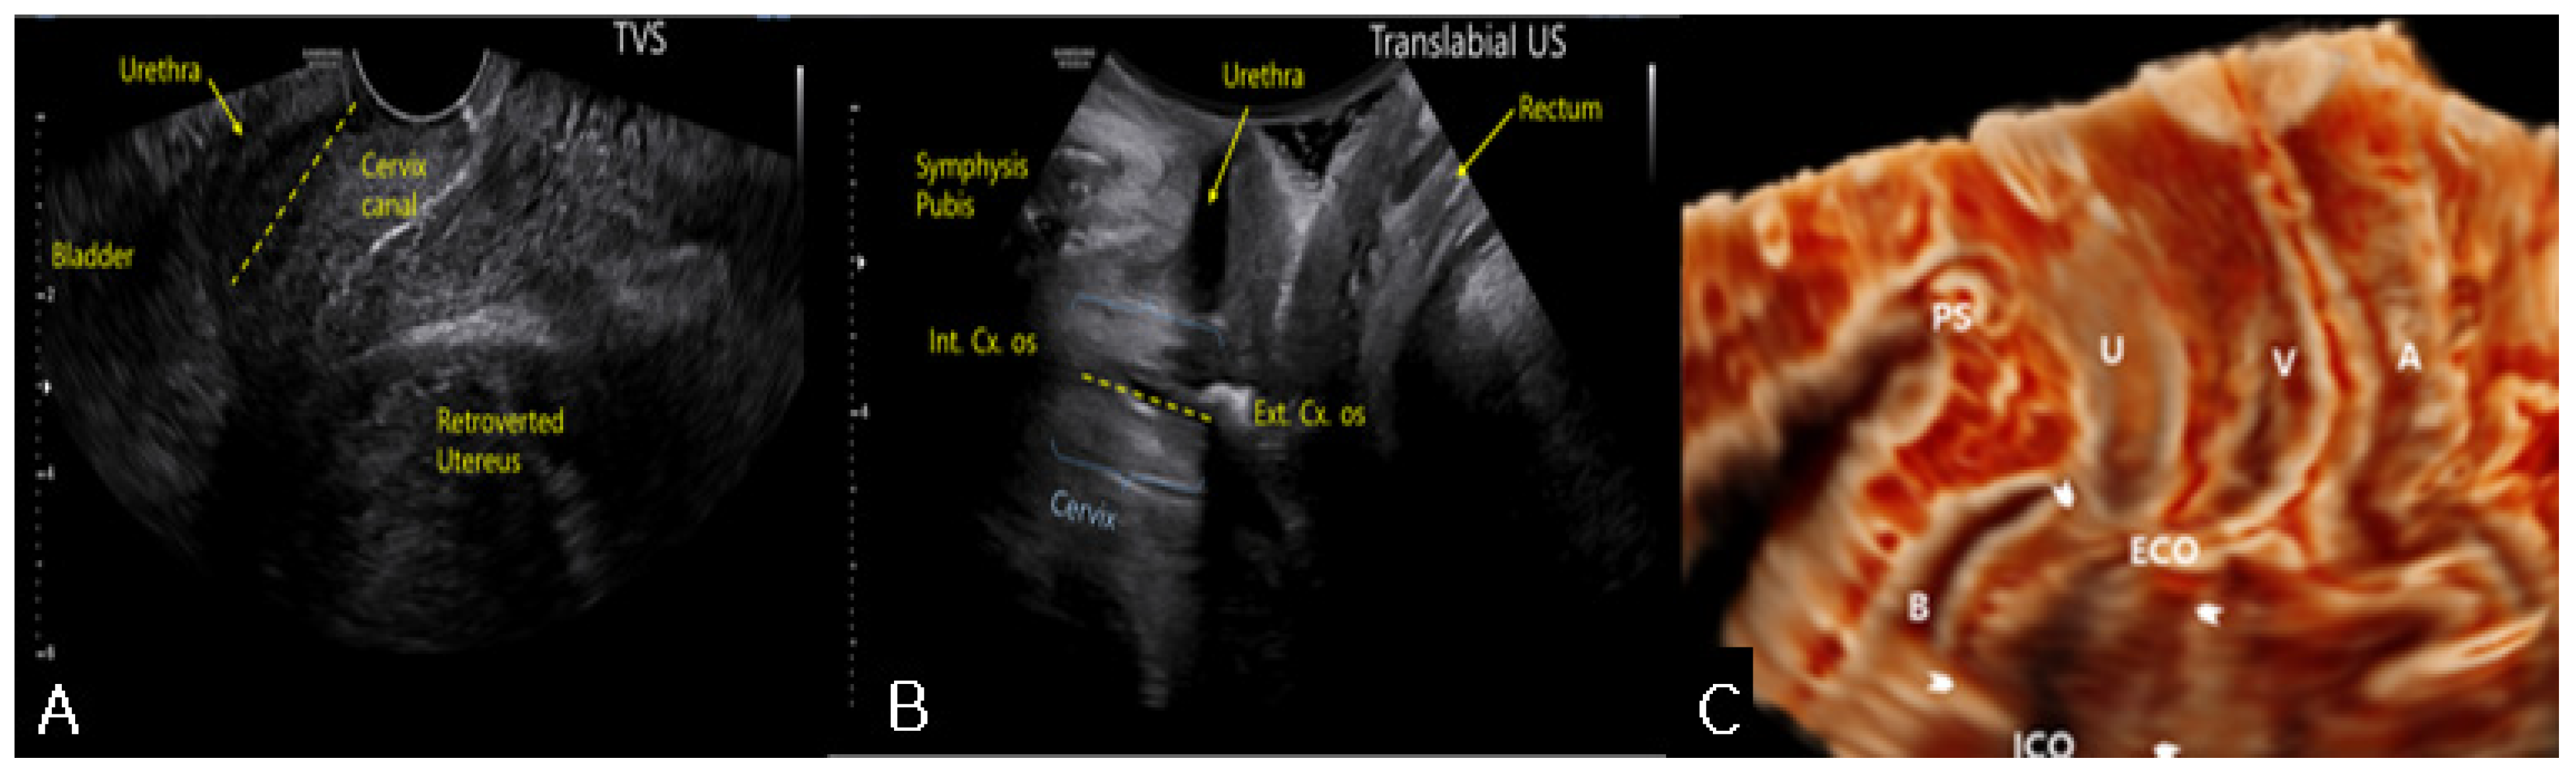

On pelvic examination, the uterine cervix was displaced anteriorly. Therefore, the cervix was out of reach and could not be exposed on vaginal examination. Sonography revealed an 18 × 7-cm retroflexed fibroid uterus and an elongated uterine cervix (Figure 1A). Translabial sonography revealed that the urethra and the bladder neck were compressed by an extremely retroverted cervix (Figure 1B). In most cases, the axis of the cervix is usually perpendicular to the sonographic probe, but in this case, it was nearly horizontal to the translabial sonographic probe. The elongated ventrocranially displaced uterine cervix was compressing the urinary bladder. MRI showed this relationship between the cervix and the bladder more clearly by revealing an elongated cervix compressing the urinary bladder neck (Figure 2A) as the incarcerated uterus lifted the cervix and fixed it. In addition, the bladder, which was hourglass-shaped, was completely compressed by the cervix (Figure 2C). Manual reduction for the management of the incarcerated uterus was unsuccessful. However, the patient was able to self-void several times immediately after the procedure, clearly suggesting that the prolonged urinary obstruction was caused by the incarceration. Thus, we performed a hysterectomy to treat the uterine incarceration.

Figure 1. (A) Transvaginal sonography revealed an 18 × 7-cm sized, retroverted fibroid uterus and an elongated uterine cervix compressing the bladder neck; (B) Translabial sonography showed that the urethra and the bladder neck were compressed by extremely retroverted cervix; (C) Three-dimensional translabial sonography also demonstrated the compression of the urethra and the bladder neck (arrowhead). The elongated, ventrocranially displaced uterine cervix was compressing the urinary bladder. PS, pubis symphysis; B, Bladder; ECO, external cervical os; ICO, internal cervical os; V, vagina; A, rectum.